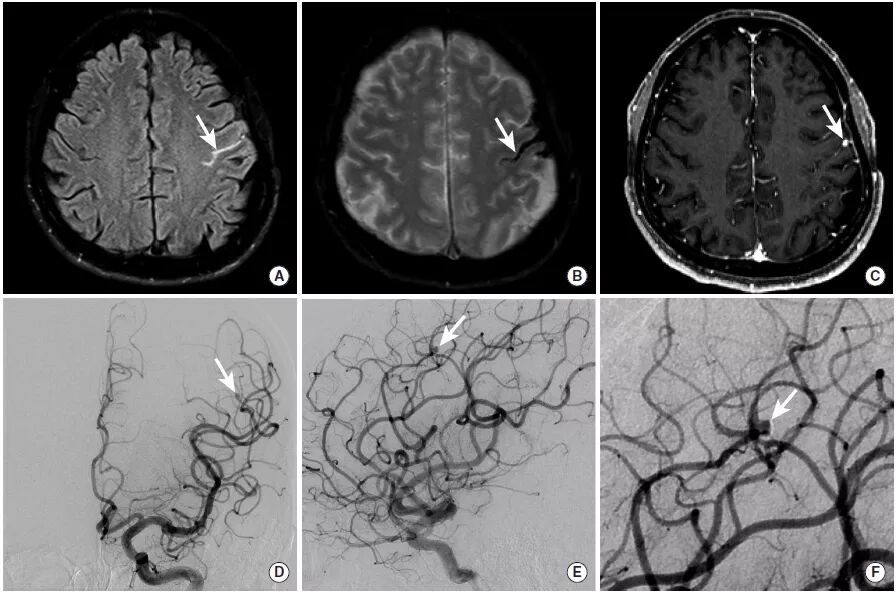

图15

高凝状态的女性患者,脑实质内出血继发于上矢状窦血栓形成。

CT平扫显示多发脑实质内出血灶(图A),MRI(图B~D)则进一步显示了脑实质的低信号出血灶,病灶周围并伴有周围高信号的

图16

中年女性,主要症状为

图A:MRI的FLAIR成像可见右缘沟内的异常高信号(长尾箭头)。

图B:GRE序列进一步证实了脑沟内异常低信号,为蛛网膜下腔出血(长尾箭头)。

图C、D:DSA显示右侧大脑中动脉M4段(长尾箭头)和右侧大脑前动脉远端(未示出)微小的串珠样改变,与血管炎表现一致。